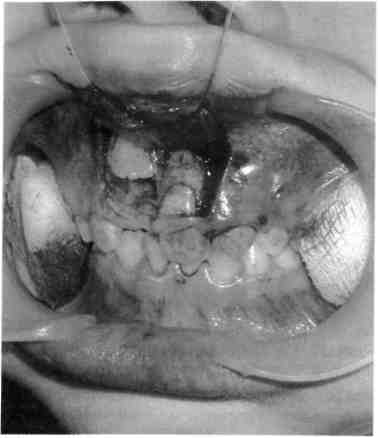

Переломы переднего отдела аль­веолярной части верхней и нижней челюстей занимают одно из первых мест среди других повреждений ли­цевых костей. Они сопровождаются разрывами слизистой оболочки и подлежащих мягких тканей, а также

вывихом или переломом зубов. Иногда вместе с травмированным альвеолярным отростком смещают­ся фолликулы постоянных зубов. Они нередко погибают. Смещение отломанного альвеолярного отрост­ка приводит к нарушению прикуса (рис. 10.18).

Такие переломы чаще бывают у детей 8— 11 лет. При переломах аль­веолярного отростка сила воздейст­вия распространяется на участок небольшой протяженности, как правило в переднем отделе. Этот вид травмы участился вследствие агрессивных игр на улице (катание на роликах, качелях). Анатомиче­ское положение альвеолярного от­ростка, неполный зубной ряд у де­тей этого возраста часто способст­вуют открытому повреждению. Травмированный фрагмент может быть очень подвижен, что наблюда­ется при полных переломах, огра­ниченно подвижен, иметь различ­ное положение (что придано на­правлением удара) внутрь полости рта, в сторону, кпереди. Всегда от­мечается дизокклюзия зубов.

Рис. 10.18. Перелом альвеолярного от­ростка верхней челюсти соответственно фронтальной группе зубов.